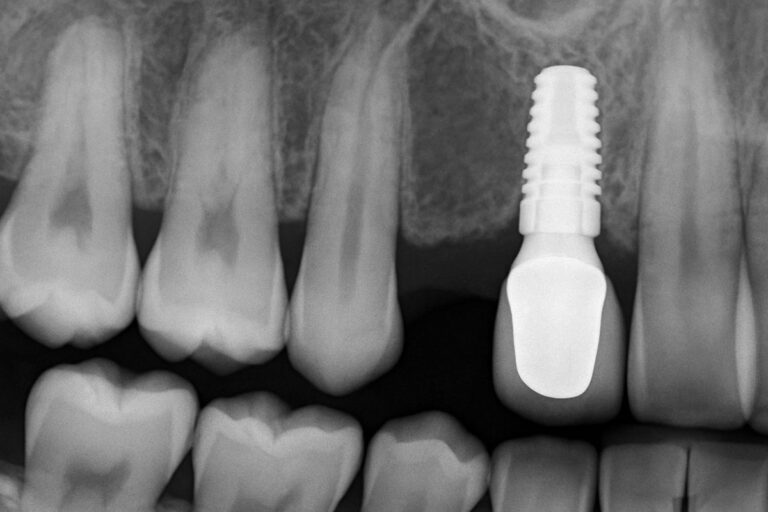

Abutment placement in Berkeley, CA is the step that connects a dental implant to the replacement tooth. If you have a dental implant or are